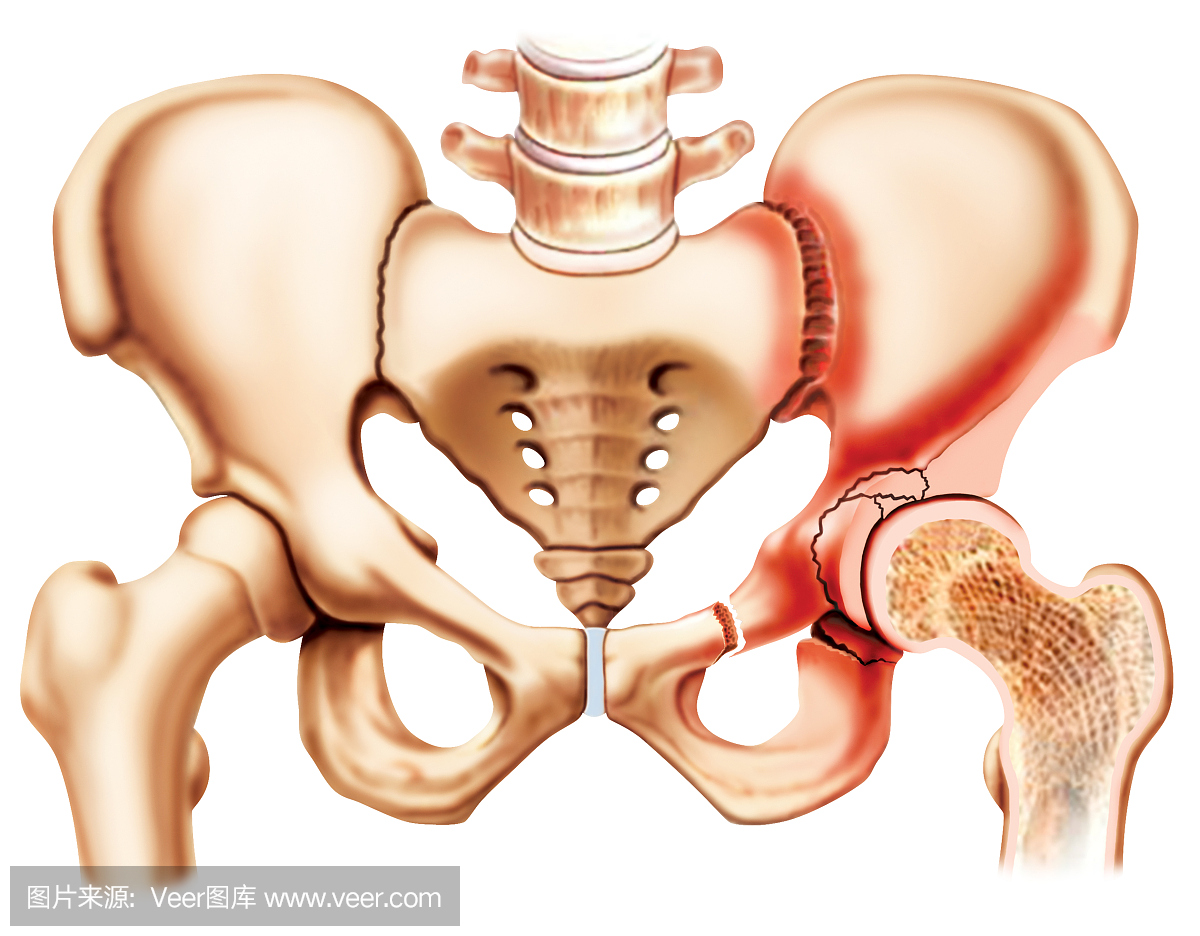

髋关节后脱位合并髋臼骨折切开复位术

髋关节后脱位合并髋臼骨折切开复位术

300x308 - 13KB - JPEG